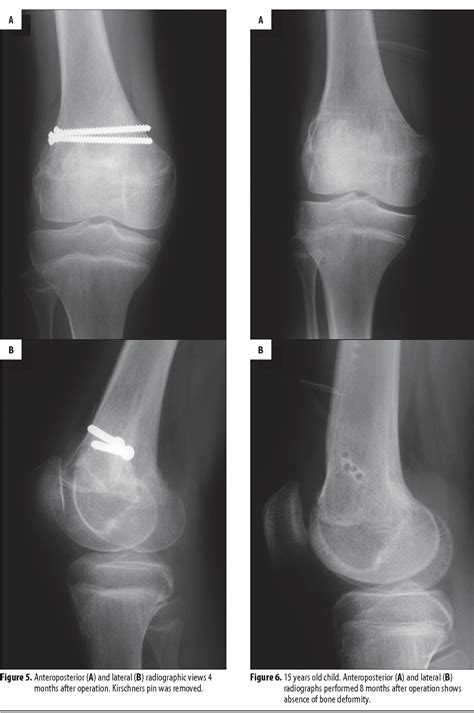

The Salter-Harris classification system is the gold standard for describing fractures involving the growth plate in children. A Salter Harris Type II fracture specifically describes a break that travels through the growth plate (physis) and exits through the metaphysis—the portion of the bone directly adjacent to the growth plate. This creates a characteristic triangular-shaped fragment of the metaphysis, often referred to as the Thurston Holland sign on an X-ray.

Because the fracture line moves through the physis and then splits the bone shaft, it essentially separates the growth plate from the main shaft of the bone while leaving the plate attached to the epiphysis (the end of the bone). This specific configuration is generally considered more stable than other types, such as Type III or IV, which cross into the joint space.

Radiographic evidence is crucial. While a standard X-ray will usually reveal the Salter Harris Type II fracture, subtle cases might require comparing the injured limb with the uninjured side. In some instances, the fracture may be nondisplaced, making it look like a simple soft tissue injury; however, if there is persistent pain, follow-up imaging is mandatory.

• Monitoring: Periodic X-rays are taken to ensure the bone remains aligned and to monitor for any signs of premature growth plate closure.

In rare cases where the bone is severely displaced or cannot be aligned manually, surgical intervention with pins or screws may be required to hold the growth plate in the correct position until healing occurs.